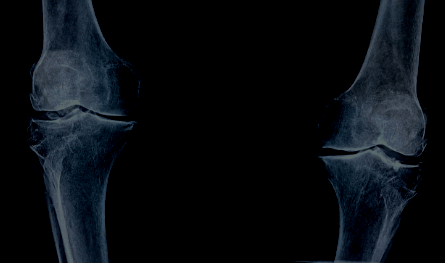

In this revisit to the table (Step 5 in our problem-solving process), Tiffany, Katie, Effie, Eileen, and Kerry discuss the many layers around the word “arthritis” including: 1) Misunderstandings around the word that can lead to delays in diagnosis, family and friend judgements, and the different type associated with “AUTO” diseases; and 2) Complexities that exist when trying to identify the AiArthritis from other potential comorbidities (Osteoarthritis, bursitis, enthesitis) and how clarity about this could help with detection, access to the right treatments, and overall better health outcomes.

This conversation takes many turns, all which address issues identified from lived patient experience. Why is differentiating arthritis types important? How many of us referenced family history to expedite diagnosis? How does public, family, and even doctor misunderstanding of our diseases play into diagnosis and exploring potential comorbidities? How accurate is the literature in regards to arthritis prevalence in comparison to what patients report to be true? They even started brainstorming the development of a new tool that could help the public, patients, and health providers better understand the layers of our diseases as well improve communication and overall disease journeys.

- 31:11 There are different kinds of arthritis and some of us have more than one, which can lead to confusion in diagnosis (“You’re too young to have arthritis”, “You’re too old to have RA”) and family misunderstandings (“oh I have that too, it’s not that bad”). They discuss why it’s important for patients to know which type they have - or if they have more than one type. Also, how do we differentiate the systemic systems (part of our disease or comorbidity?)

- What disease do I have? How can this resource be used to share with doctor?